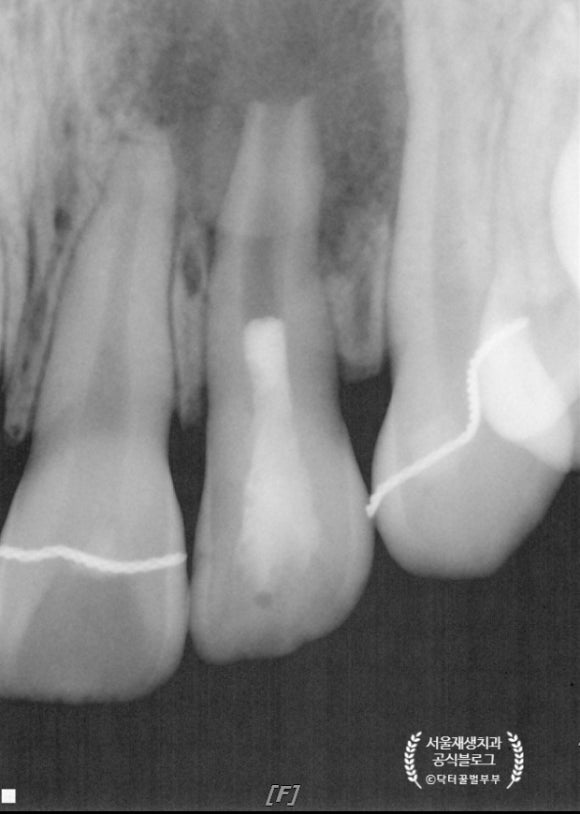

4개월 후에 왔습니다.

햇살 무늬처럼 가장자리에서부터 뼈가 재생되는 것, 이제는 보이시지요?^^